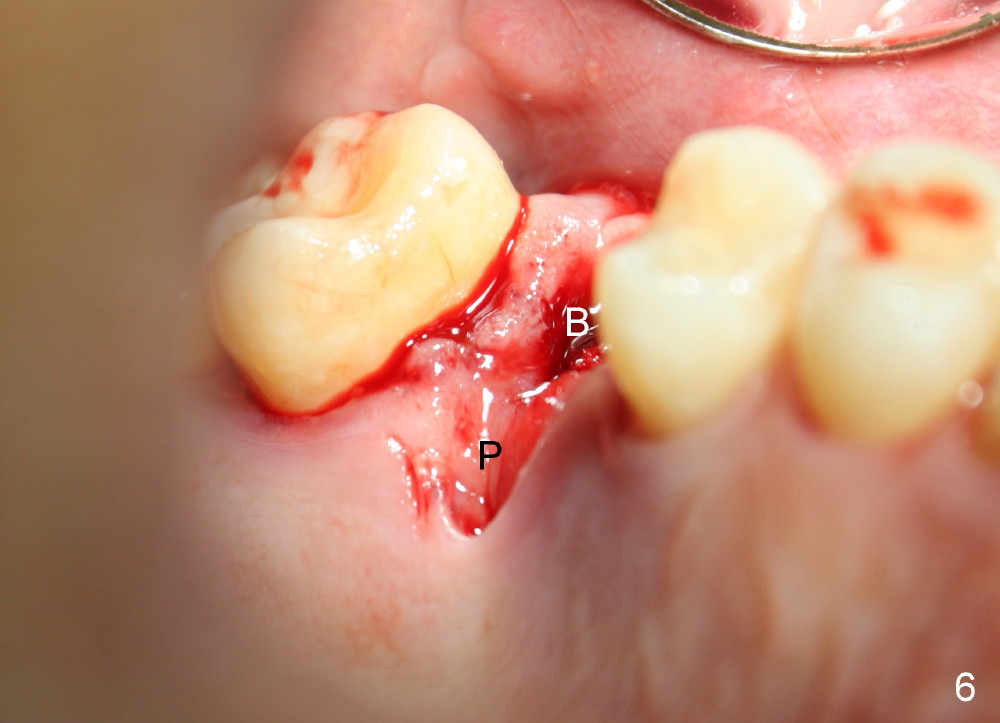

The tooth #3 has severe periodontitis with probably endodontic lesion (Fig.1,2). The patient is a 43-year-old man with apprehension of dentistry. An acute infection causes pain and tooth shift (Fig.4,5). A 7x17 mm immediate implant is planned (Fig.3). The palatal socket is shallow (Fig.6 P), corresponding to severe recessive palatal root (Fig.5 P). The osteotomy is created mainly in the buccal socket (Fig.6 B), exactly in the lingual slope of the septum. Initially osteotomes are used, followed by tap placement (Fig.7 T (4.5x20 mm at the depth of 17 mm). When the implant is placed as planned (Fig.8 I), there is more vertical contact (Fig.8 red line) than that associated with the tap (Fig.7 red line). The corresponding insertion torque is between 50 and 60 Ncm. There is only one small gap buccally, which is filled with bone graft (Fig.9 <). After the insertion of a short abutments with vertical slots (Fig.9,10 A), perio dressing is used to cover the wound. The palatal socket is expected to heal uneventfully (Fig.10 P). In fact, it does in 7 days (Fig.12 P); the bone graft in the mesiobuccal aspect is healing and stabilized (Fig.11 <). By two weeks postop, the mesiobuccal socket has healed (Fig.13 <). With removal of a diseased tooth, our body has amazing power to heal.